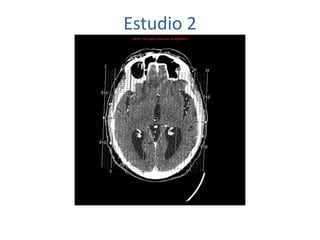

Estudio 2

• Estudio sin y con contraste, con reconstrucciones sagitales y coronales

del estudio con contraste.

Se observa una lesión ocupante de espacio en lóbulo frontal derecho que

presenta un tamaño de 18 x 32 x 22 mm (cc x ap x tr), bilobulada, no del

todo bien delimitada, con realce en anillo irregular, con hipocaptación

central, probablemente por necrosis, y asociada a un extenso edema

vasogénico con efecto masa tanto sobre los surcos de la convexidad

como sobre la cisterna insular, el sistema ventricular y la línea media,

esta última con un desplazamiento de 5 mm a la altura del septo

interventricular.

No se aprecian otras lesiones focales intra o extraaxiales de significación

patológica.

Habría que considerar como primera posibilidad que se tratase de una

lesión metastásica, por bien un tumor primario, aunque no se puede

descartar otras opciones, sin imprescindible correlación con la clínica y

con sus antecedentes.